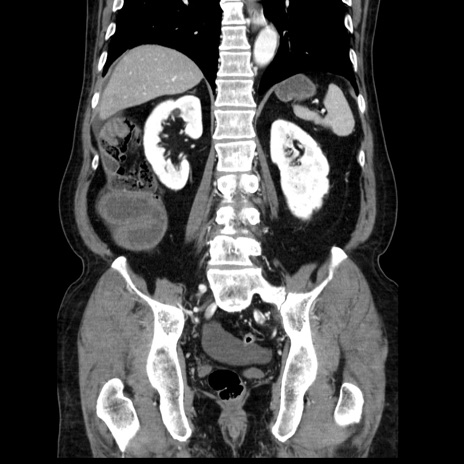

症例30(冠状断像)

【症例】80歳代男性

【主訴】臍周囲痛

【現病歴】約6時間前から臍下部痛が出現。次第に腹部膨隆・背部痛も生じてきたため来院。背部痛の場所は変化しない。

【身体所見】意識清明、BT 36.3℃、BP  131/87mmHg、P 87bpm、SpO2 100%(RA)、臍周囲自発痛・圧痛あり、反跳痛なし、自発痛部位に一致して板状硬あり、腹部膨隆、腸雑音減弱、CVA tenderness両側陰性。

【データ】WBC 19600、CRP 0.33